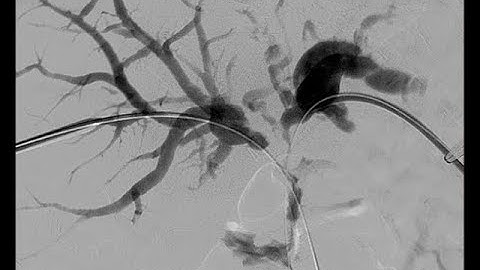

Percutaneous transhepatic cholangioscopy